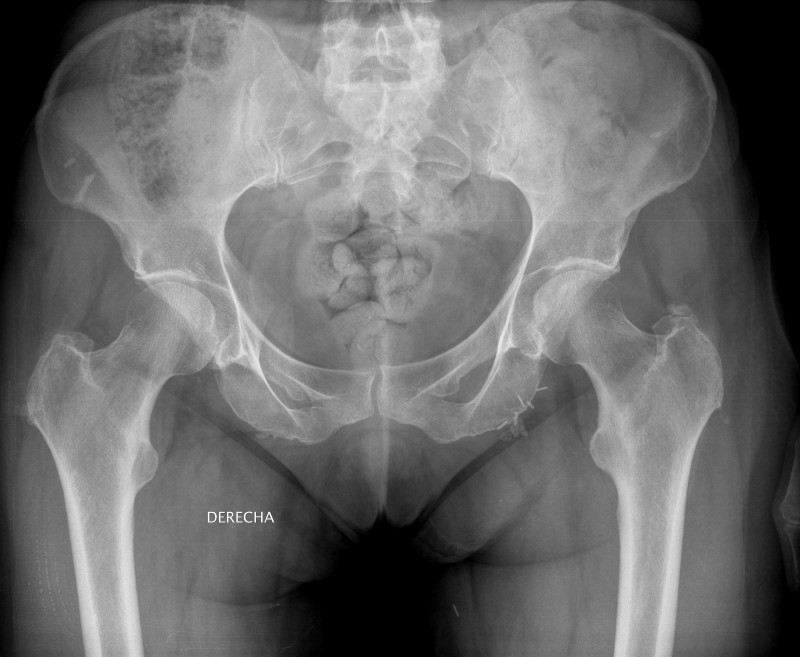

A Plataforma SOS Sanidade Pública de Compostela presentou este mércores unha denuncia contra a consellaría de Sanidade nos Xulgados de Fontiñas pola mala calidade das agullas usadas para inxeccións de insulina. As e os representantes da Plataforma adxuntaron, entre outras probas, radiografías dunha doente con 5 agullas cravadas no abdome e denuncias feitas polos doentes perante diferentes organismos e institucións como Sanidade, a Xerencia de Xestión Integrada e a Valedora do Pobo.

Denuncian ademais que se dobran, causando desgarros ao retirarse do corpo, o que provoca “dor intensa, sangramentos, hematomas, abscesos e inchazo”. E non só iso, aseguran tamén que “parten dentro do corpo do doente, requiríndose en moitas ocasións intervencións cirúrxicas para extraer a agulla” e producen edemas en doentes que, en moitos casos, deben auto-inxectarse insulina dúas ou tres veces ao día. Isto xunto con problemas psicolóxicos, sobre todo en nenos con medo a pincharse polo dor.